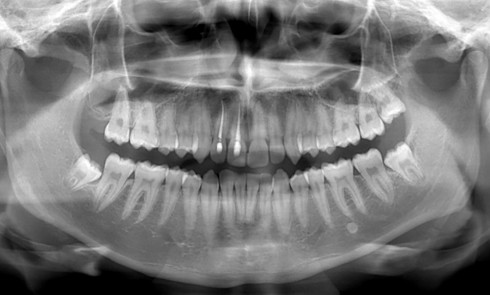

Les protocoles d’extraction-implantation immédiate, décrits pour la première fois en 1976 par Schulte et Heimke [1], se sont progressivement développés...